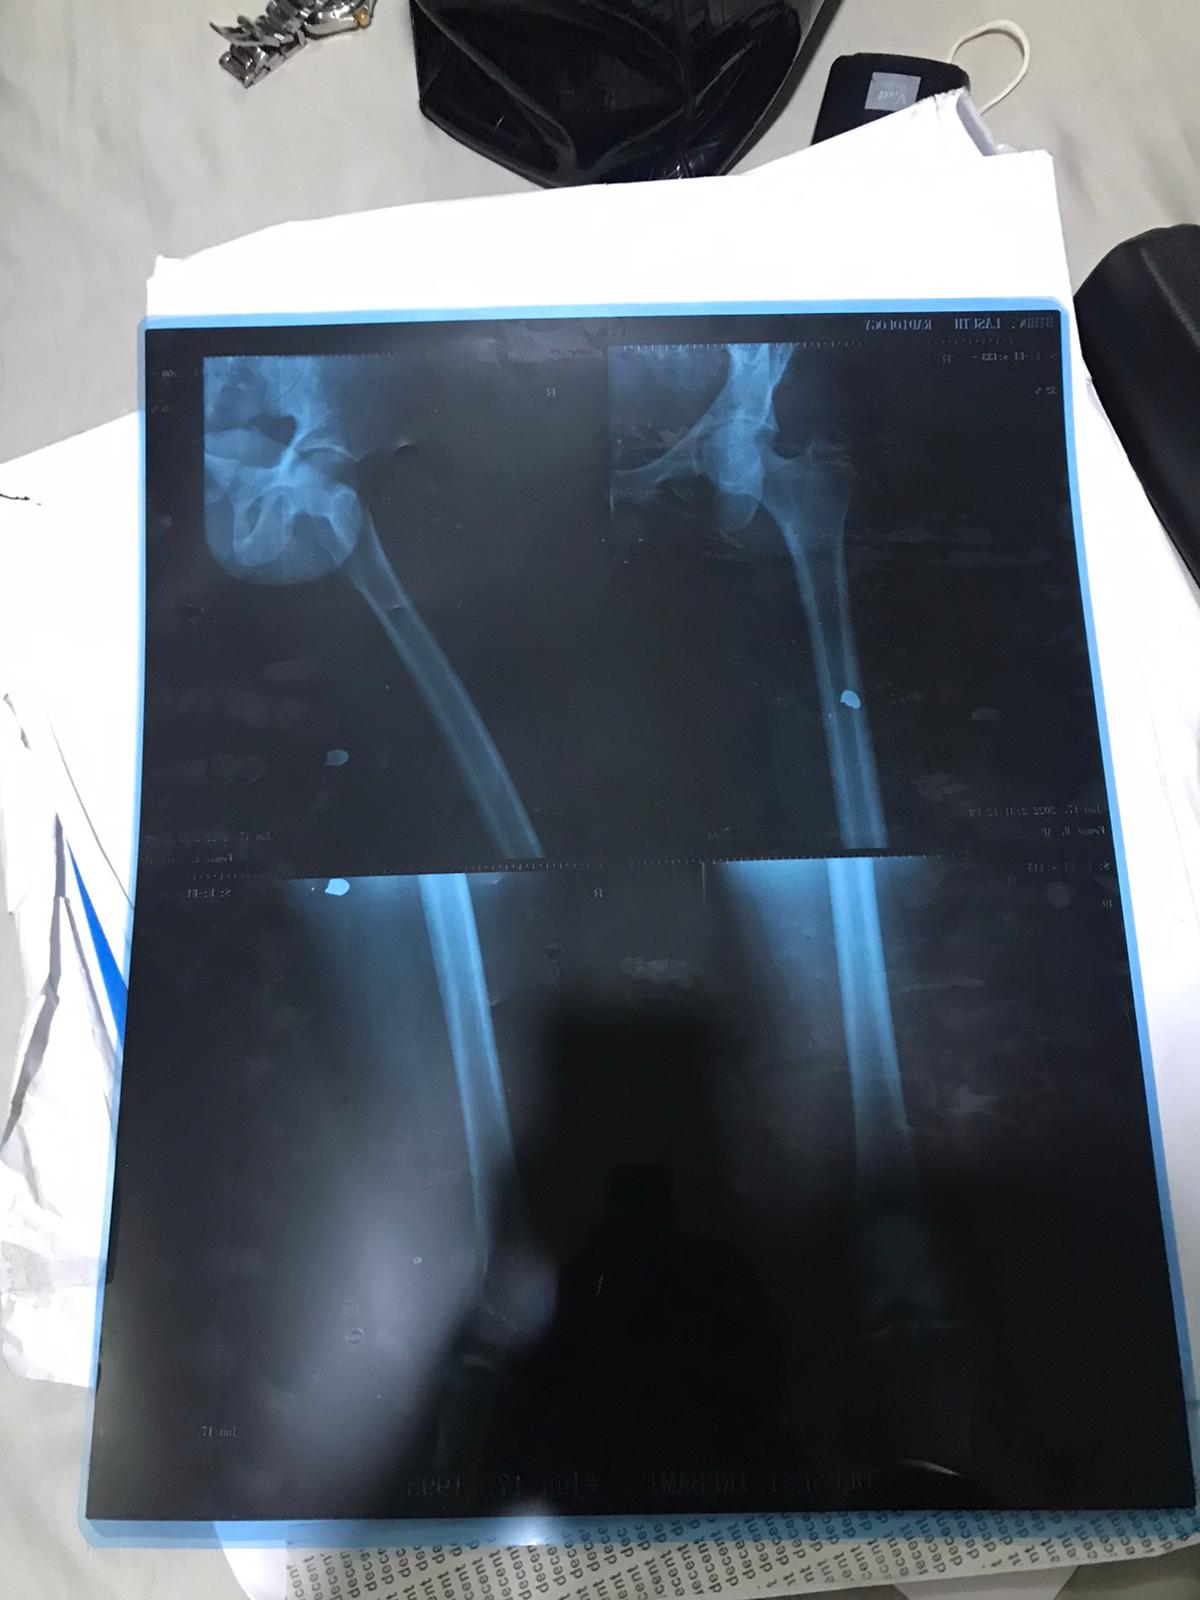

“The images above are of the bullet hole left in the thigh of Irebami Lawrence on the night of June 8, during an altercation with Burna Boy’s posse, as was widely reported. The night started this way.

“I spoke to several firearms experts who confirmed that the gun in the picture is a Glock 19 handgun, whose ammunition profile is consistent with that of the size of the holes made in the iPhone and Irebami’s thigh in the opening tweet.